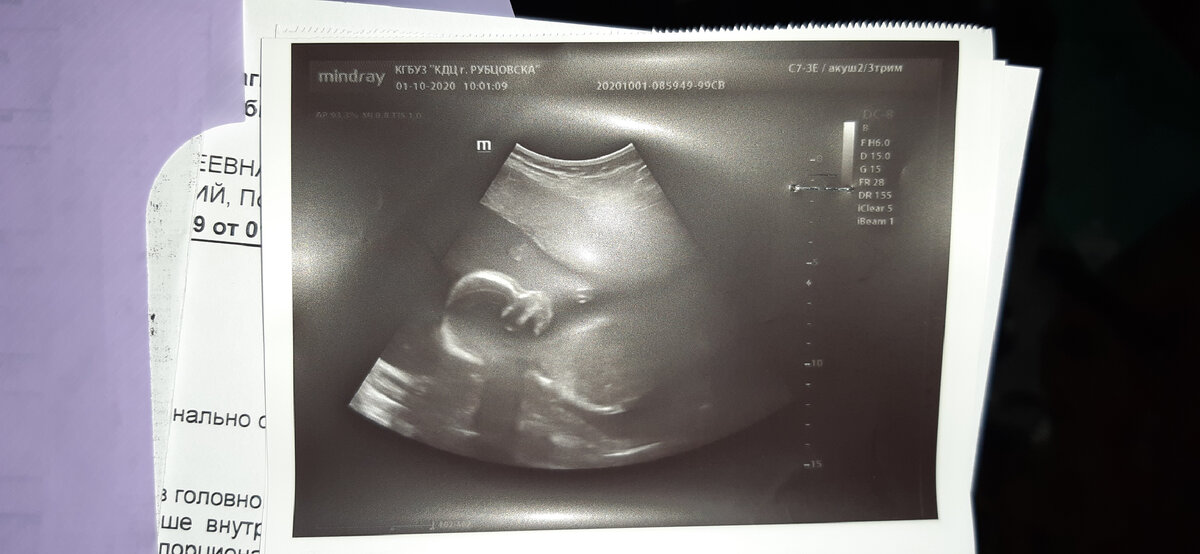

Я пошла на УЗИ. Я очень надеялась, что малышка сама распуталась и обвития уже не покажет.

Сделали УЗИ, я спросила про обвитие, но оно так и осталось, зато не было нарушения кровотока. Получается, зря меня туда отправили?